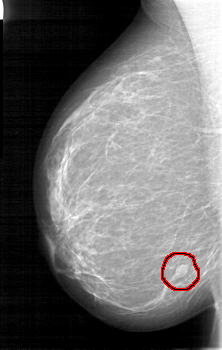

FILE: D_4090_1.RIGHT_MLO.OVERLAY

TOTAL_ABNORMALITIES 1

ABNORMALITY 1

LESION_TYPE MASS SHAPE OVAL MARGINS ILL_DEFINED

ASSESSMENT 0

SUBTLETY 5

PATHOLOGY BENIGN

TOTAL_OUTLINES 1

BOUNDARY

RIGHT_MLO LINES 5236 PIXELS_PER_LINE 3316 BITS_PER_PIXEL 12 RESOLUTION 43.5 OVERLAY